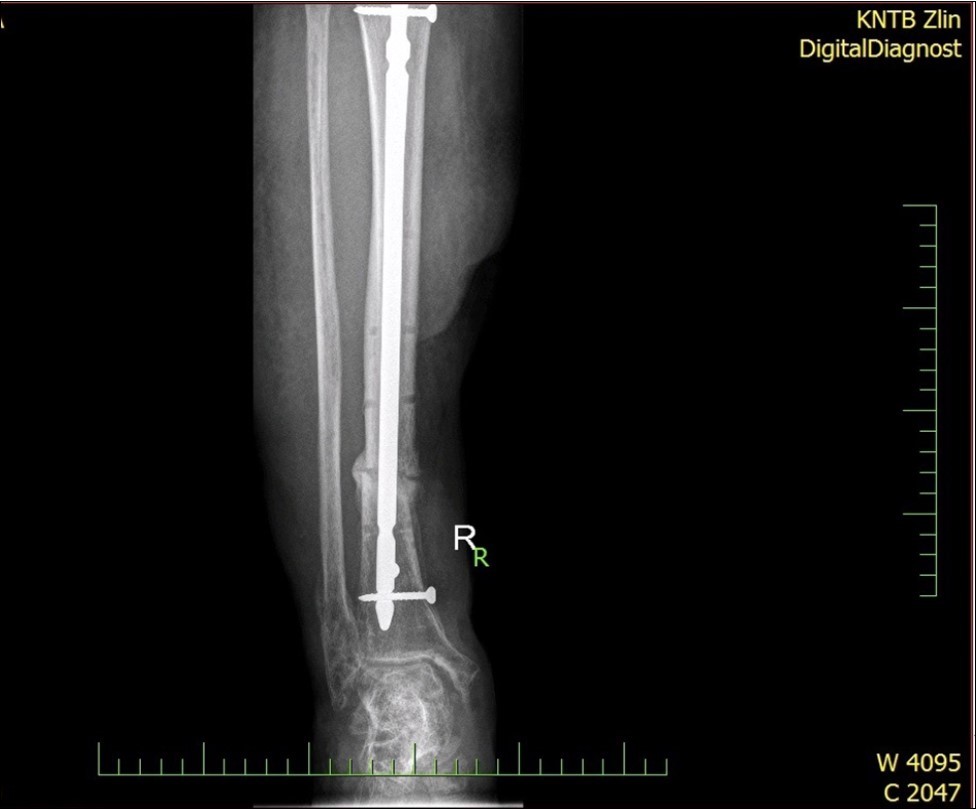

Figure 28.23 April. Surgery conversion of osteosynthesis. Removal external fixator and implantation intramedullary tibial nail. Gradual bone healing - last X-ray september 2019

Figure 29.23 April. Surgery conversion of osteosynthesis. Removal external fixator and implantation intramedullary tibial nail. Gradual bone healing - last X-ray september 2019